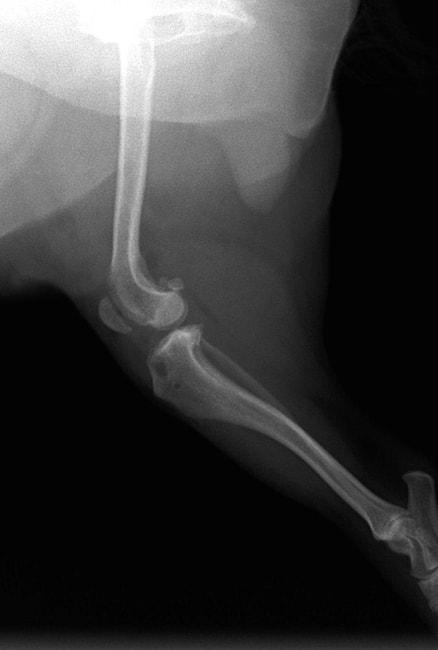

■ 症例24 キャバリア 7か月

左右膝蓋骨内方脱臼(左:グレードⅣ 右:グレードⅢ)

以前から左右後肢の跛行が認められ、整形外科学的検査・レントゲン検査により左右の膝蓋骨脱臼が認められた。症状が重度である左膝の膝蓋骨脱臼整復術を行った。外科手技は縫工筋及び内側広筋の解放、脛骨粗面の外側転位、滑車ブロック形造溝術、内外側関節方の縫縮を実施した。術後一か月時点で、左の膝蓋骨は安定しており経過は良好である。

本症例は成長期における重度の膝蓋骨脱臼であり、術後の再発の可能性もあるため、経過をしっかりと観察していく必要がある。また、今回手術を実施していない右膝に関しても経過を観察し、手術を検討していくこととする。